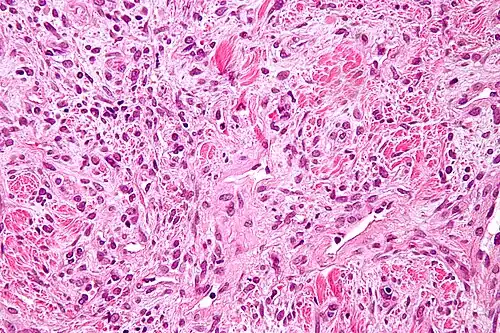

Histologie

Les tumeurs fibreuses solitaires sont constituées de cellules mésenchymateuses, de différenciation fibroblastique[6]. Elles sont ovoïdes ou fusiformes. Leur cytoplasme est riche en collagène[3]. L'architecture tissulaire est hétérogène, supportée par un tissu conjonctif collagénique et alterne entre des zones bien fournies en cellules et des zones plus pauvres, où l'espace intercellulaire est plus riche en acide hyaluronique[3].

L'immunohistochimie retrouve l'antigène CD34 dans 80 % des cas[30], ce qui permet de différencier les tumeurs fibreuses solitaires des mésothéliomes[3]. Les tumeurs expriment également la vimentine, mais aucune des cytokératines[30].

Aspect en microscopie optique (coloration H&E).